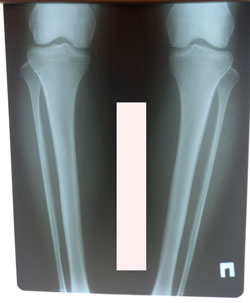

Исходник - 23 года.

Дата операции - 03.02.2021

image-18-02-21-05-32-1.jpg

image-03-02-21-12-27.jpg